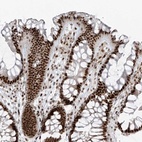

Immunohistochemical staining of human colon shows strong nuclear positivity in glandular cells.